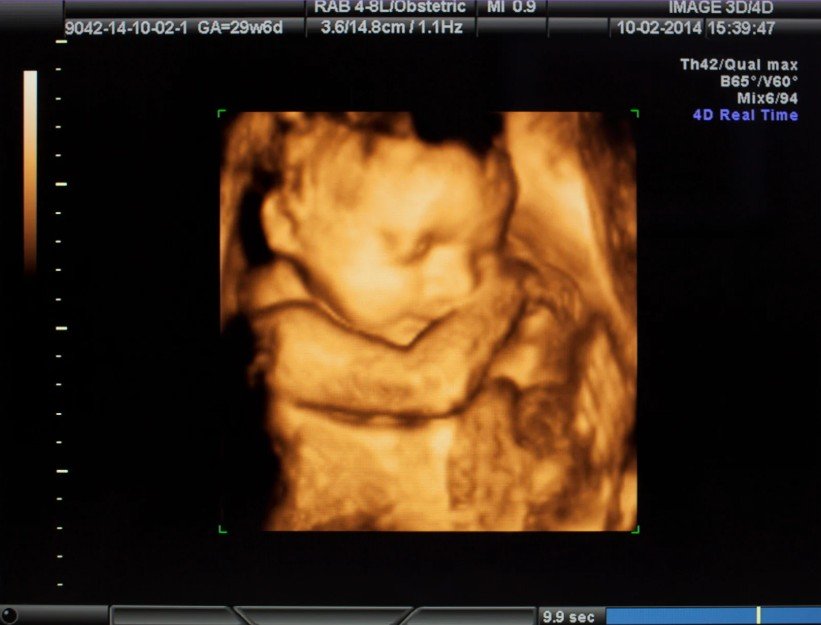

La atención incluye ecografías periódicas con tecnología 4D, ofreciendo imágenes y vídeo para que los futuros padres puedan ver la evolución del bebé con la máxima calidad. Estas exploraciones permiten valorar con detalle su crecimiento, posición y bienestar general.

En esta fase se realiza la ecografía morfológica, habitualmente entre las semanas 18 y 22. Esta exploración permite estudiar con detalle la anatomía y el desarrollo del bebé, valorar el crecimiento de cada estructura y detectar posibles alteraciones fetales. Es una prueba clave para confirmar que la gestación evoluciona de forma adecuada y para orientar cualquier necesidad de seguimiento específico.

Embrión a las 14 semanas

Cara a las 23 semanas